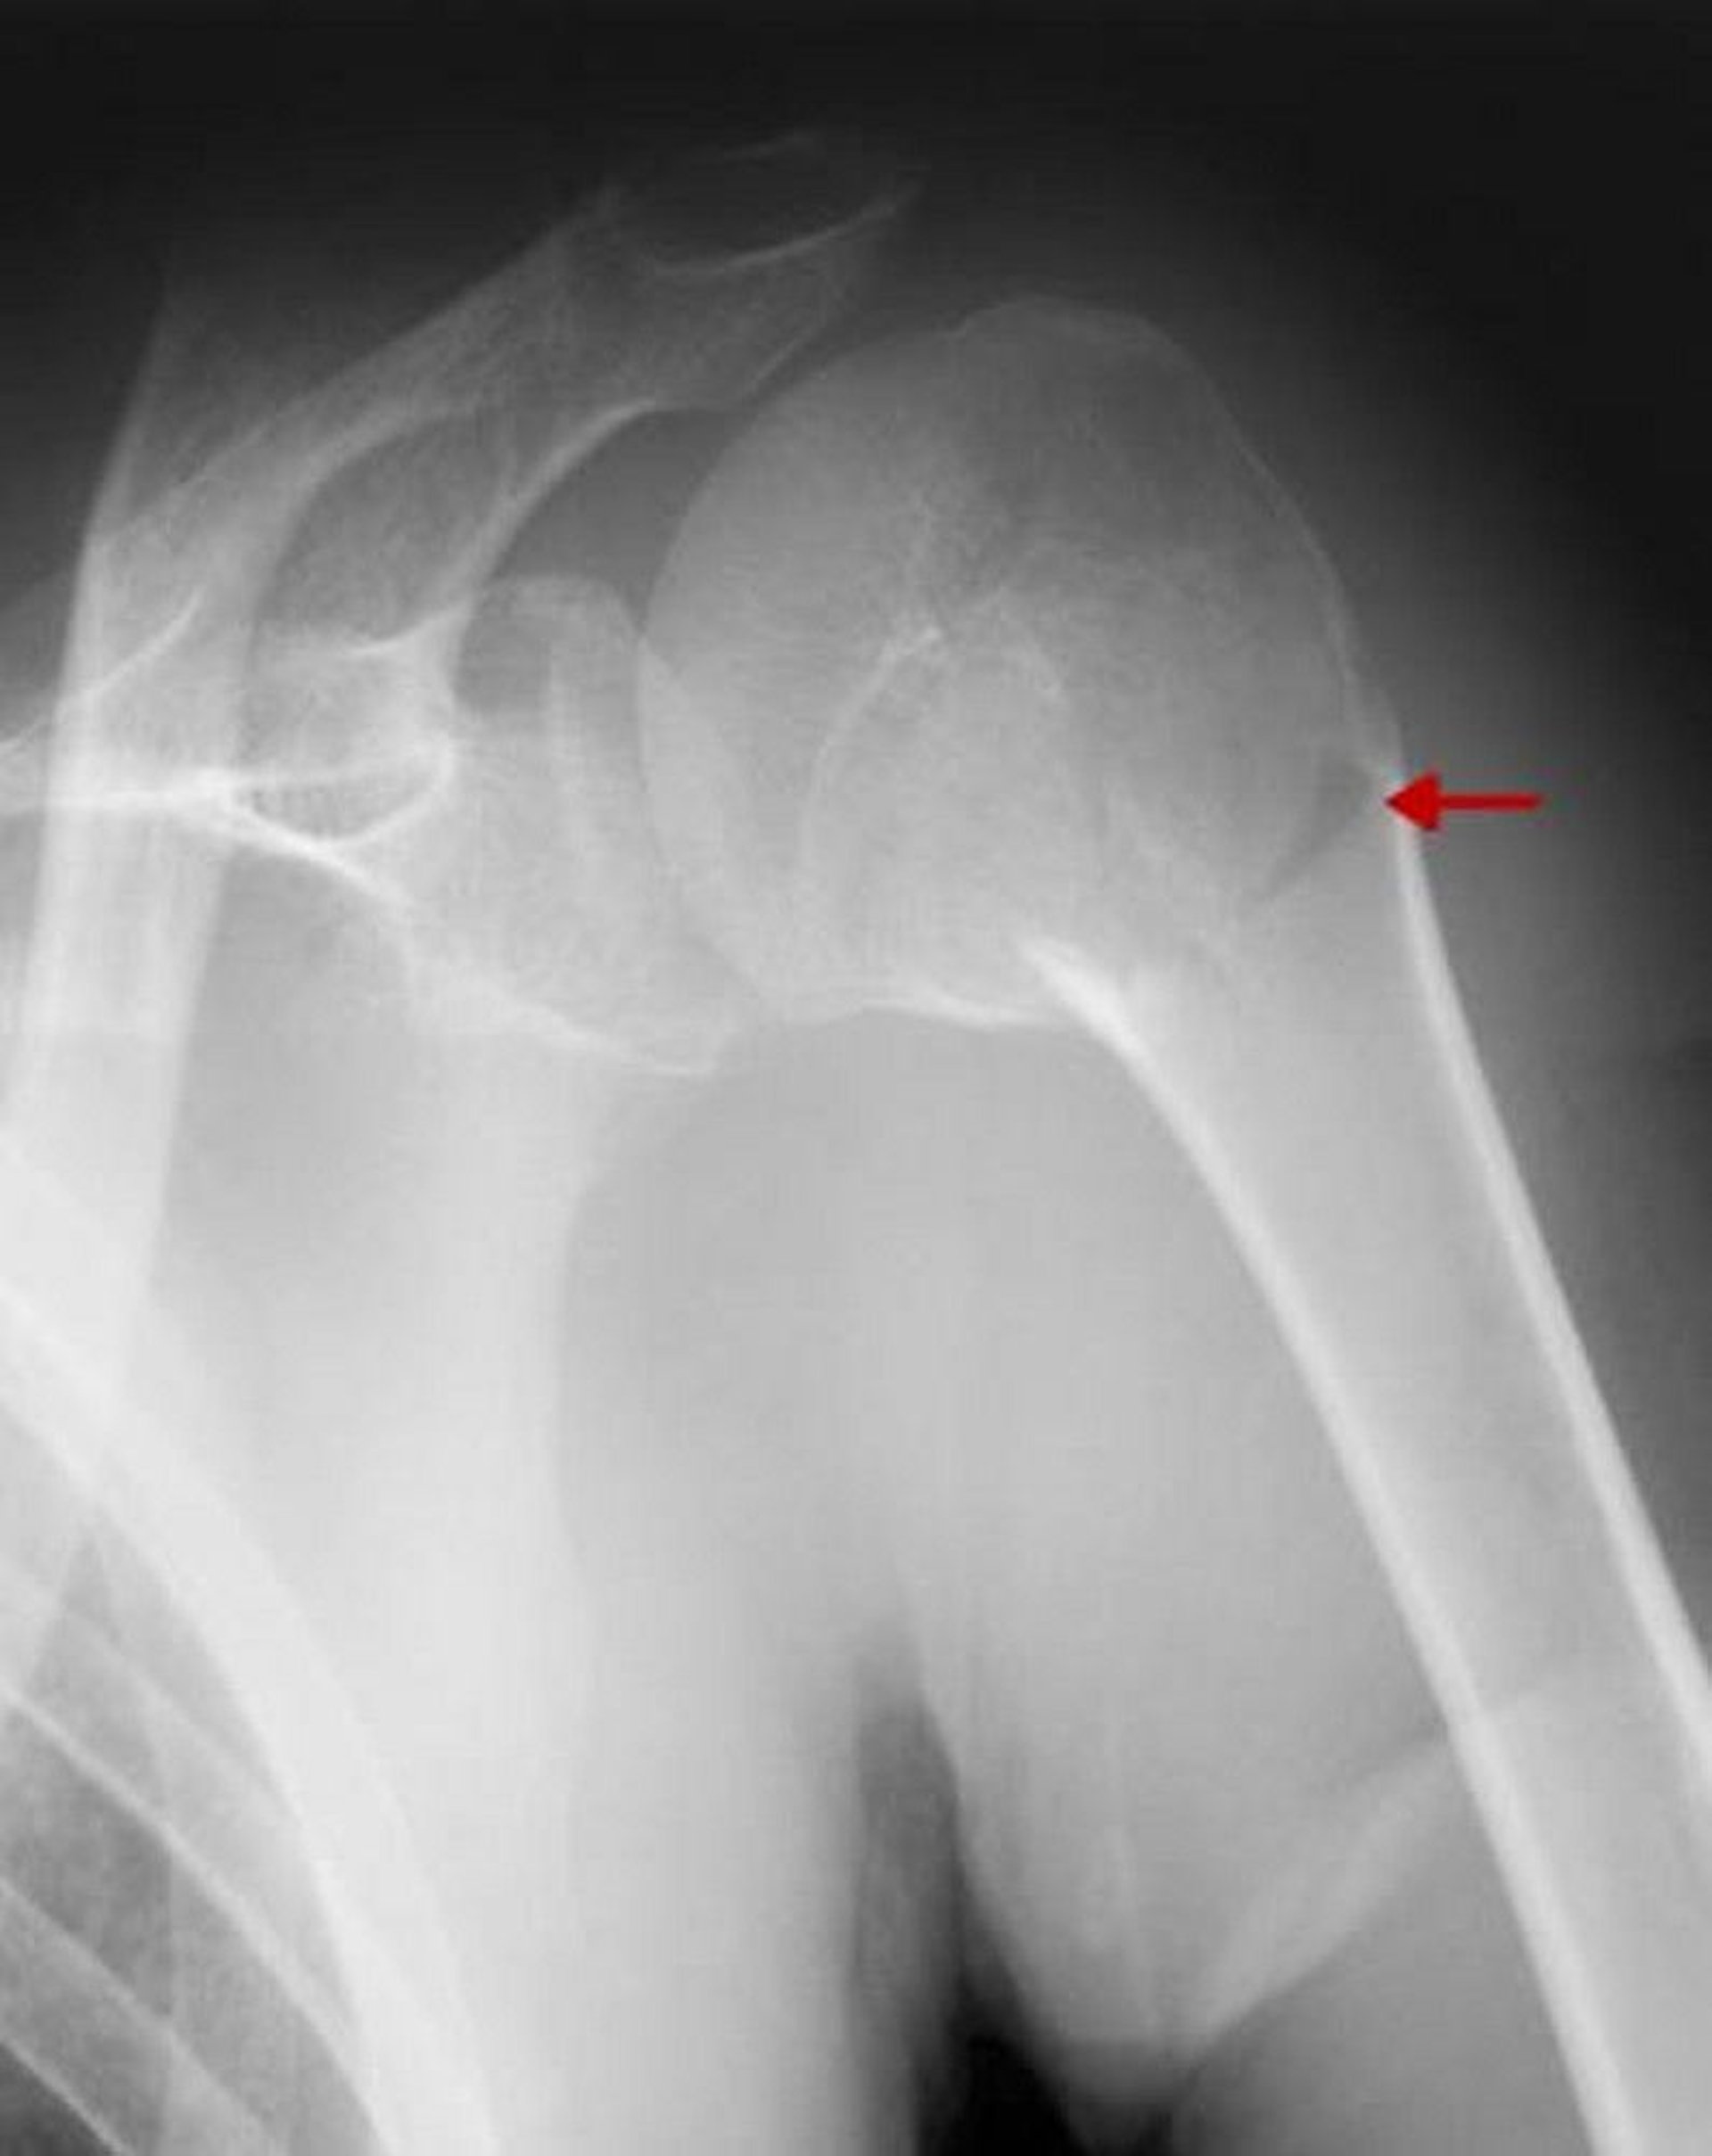

Proximal Humerus Fracture

This fracture involves the surgical neck. Because there is no significant displacement or angulation >45°, it is a one-part fracture.

ZEPHYR/SCIENCE PHOTO LIBRARY